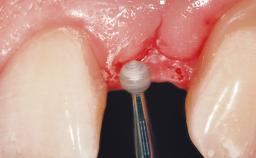

Surgical treatment of a 68-year-old female patient with a distal extension situation in the left mandible. As the CBCT analysis reveals, the bone crest anatomy in the area is not ideal and necessitates an augmentation procedure to achieve a good long-term prognosis for the planned implants and their prostheses.

After the placement of three diameter-reduced two-piece implants the bone is augmented with autologous bone chips and DBBM particles to enlarge the crest volume. The surgery is completed with the application of two membrane layers and primary wound closure.